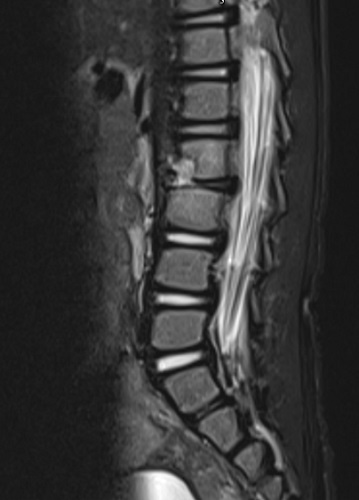

Lactante de 17 meses, previamente sano, que acude a urgencias por rechazo a apoyar el pie derecho, sin puntos dolorosos ni tumefacción y movilidad articular conservada. Analítica con leucocitosis (17 000/mm3) sin aumento de reactantes de fase aguda (RFA); radiografía de pelvis y ecografía de caderas normales. Cuadro catarral febril y otitis media aguda dos semanas antes, tratada con amoxicilina una semana, iniciándose la cojera tras finalizar tratamiento. 48 horas después es reevaluado por su pediatra con exploración normal. Pasadas dos semanas, acude de nuevo a su pediatra por estreñimiento, decaimiento e irritabilidad, asociando rechazo a la sedestación. En la exploración física, tendencia al arqueamiento de espalda con rechazo a la bipedestación y abdomen distendido. Se deriva a urgencias, donde se realiza ecografía abdominal sin hallazgos y se administra enema (no efectivo), dándose de alta con macrogol. Diez días más tarde acude a su pediatra por fiebre de hasta 40 °C, cuadro catarral leve y persistencia de decaimiento, rechazo a la deambulación y cojera derecha intermitente. En la exploración, irritable y postrado, rechazo a la deambulación y sedestación con hiperextensión de columna, abdomen distendido y doloroso, no hay puntos dolorosos a la espinopresión. Es derivado de nuevo a urgencias, donde, ante sospecha de infección osteoarticular, se realiza analítica con VSG elevada y RMN urgente para descartar afectación medular, observándose espondilodiscitis L2-L3 con absceso prevertebral y en psoas derecho (Figura 1). Ante estos hallazgos, se comenta con Neurocirugía y Cirugía Pediátrica, y se decide iniciar tratamiento conservador con antibioterapia intravenosa con cefotaxima y clindamicina durante 20 días, con mejoría clínica y radiológica progresiva.

Figura 1. Espondilodiscitis L2-L3 con absceso prevertebral y en psoas derecho